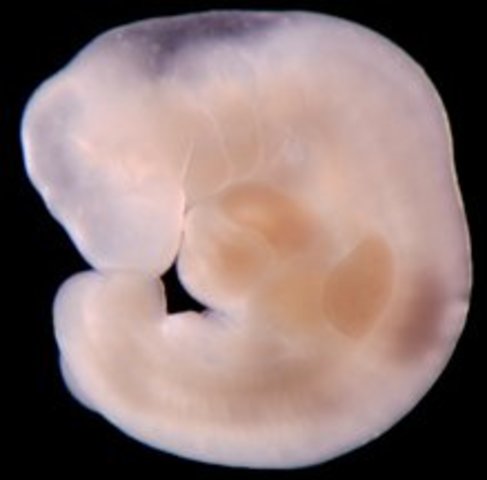

• Week 3: Cells Join, Divide - New Life Begins

Week 3: Cells Join, Divide - New Life Begins

The fertilized egg immediately begins to divide and float down into the uterus. Immediately upon fertilization your little one is set as a boy or a girl. The sex of your child is predetermined by the fathers sperm chromosomes. The cell contains all of the DNA to become a child, baby begins to form from this single fertilized egg. Cell divides itself into 2 cells, then 4, 8, and so on rapidly

• Week 4: Implantation

Week 4: Implantation

Fertilized egg is now called a blastocyst, it is a fluid filled cluster of 50-60 cells, still multiplying. Implantation occurs about day 5 to day 8 of embryo development. Embryo is only one-hundredth of an inch long. Site of implantation is where the placenta attaches to the uterine wall. After blastocyst has implanted, it will release a hormone called human gonadotropin hormone (hCG) into the blood stream